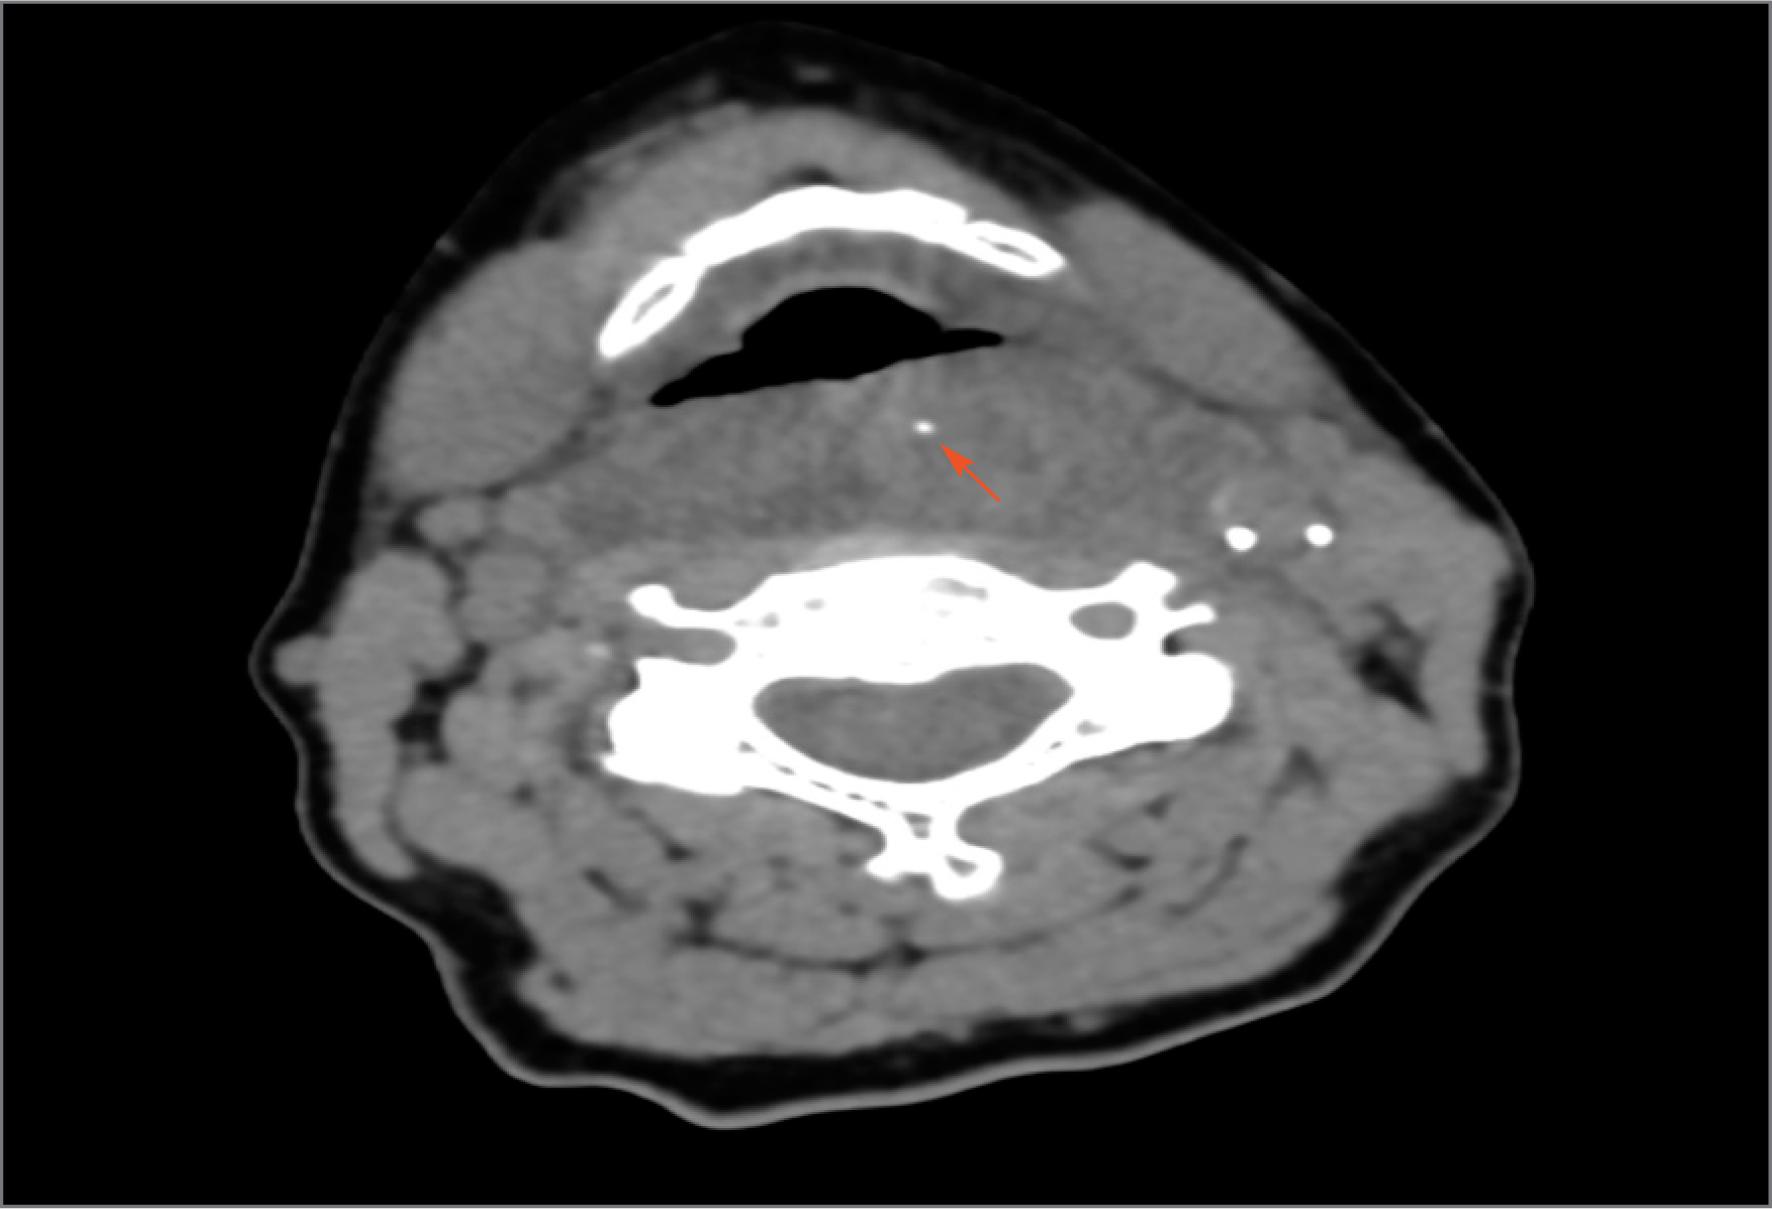

Fig. 2

CT scan, axial section, foreign body – fish bone 15 mm – arrow